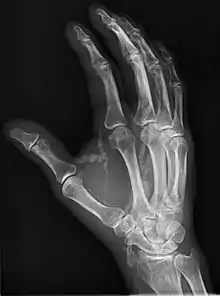

Hand radiograph showing tumoral calcinosis, PA radiograph of the right hand showing tumoral calcinosis-like metastatic calcification in a patient on dialysis. Dialysis alters calcium phosphate product (>70). Idiopathic tumoral calcinosis is autosomal dominant and is not associated with dialysis. Note the premature arterial calcification which is a clue that this is a renal patient. Vascular calcification contributes to an increase in morbidity.

Tumoral calcinosis is a rare condition in which there is calcium deposition in the soft tissue in periarticular location, around joints, outside the joint capsule.[1] They are frequently (0.5–3%) seen in patients undergoing renal dialysis. Clinically also known as hyperphosphatemic familial tumoral calcinosis (HFTC), is often caused by genetic mutations in genes that regulate phosphate physiology in the body (leading to too much phosphate (hyperphosphatemia)). Best described genes that harbour mutations in humans are FGF-23,[2] Klotho (KL),[3] or GALNT3.[4] A zebrafish animal model with reduced GALNT3 expression also showed HFTC-like phenotype,[5] indicating an evolutionary conserved mechanism that is involved in developing tumoral calcinosis.